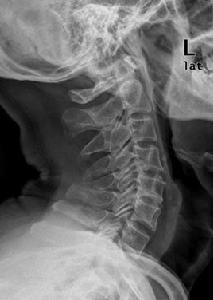

頸骨俗稱天柱骨,是頸椎骨的統稱。頭在上為天,頸椎為頭之支柱,因名。《醫宗金鑒》:“頸骨者,頭之莖骨,肩骨上際之骨,俗名天柱骨也。”一說頸骨指旋台骨。旋台骨又名頸骨、天柱骨、大椎骨等。即頸椎之第四、五、六節。《醫宗金鑒》:“旋台骨,即頭後頸骨三節也。”

頸部是人體的重要部位。頸部的上界為頭部的下界,下界即胸骨上緣、鎖骨、肩峰和第七頸椎棘突間的連線。該局部以斜方肌前緣為界,分為前方的固有頸部和後方的項部;...